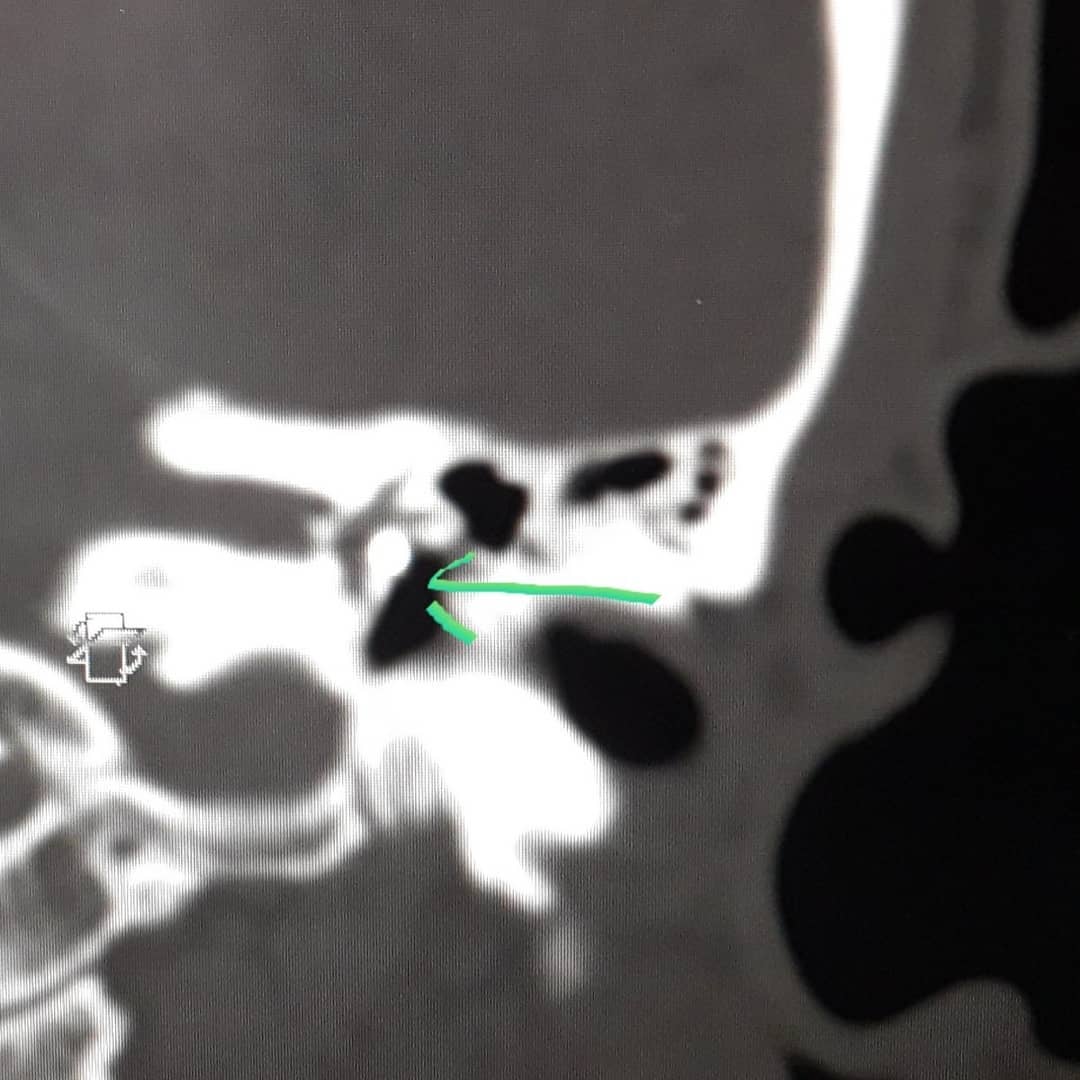

«В процессе обследования было обнаружено, что в барабанной полости за перепонкой имеются инородные тела. На КТ- снимке четко просматривались окалины, которые попали в барабанную полость в процессе проведения сварочных работ», – сообщают представители больницы в посте на своей странице в Instagram.

Под руководством заведующего отделением, главного внештатного отоларинголога Андрея Федина была проведена эндоскопическая операция. Около 45 минут врачи доставали из уха пациента металлические осколки.